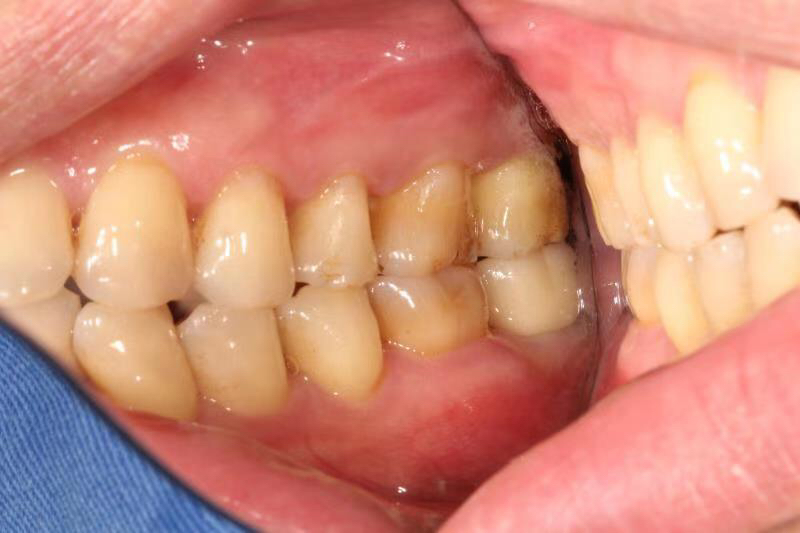

今天给大家介绍一个单颗后牙即拔即种病例。

患者中年男性,右下7号牙龋坏未及时处理至残根无法修复,CT检查发现骨量尚可,可以即拔即种,并且不需要植骨,节省了患者治疗周期,整个治疗过程用了4个月患者就戴上了牙齿。